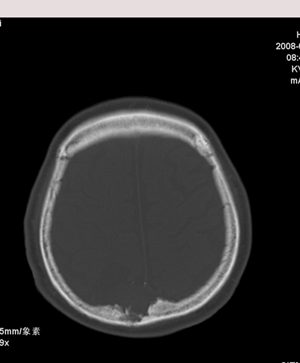

肢体活动肌力均正常。临床印象:脑血管病变。ct意见:脑软化灶,腔梗,请看看枕部病变是脑膜瘤,血管畸形还是其它

颅骨吸收破坏,病灶密度不均,周围见低密度水肿带,多考虑恶性脑膜瘤。

颅骨吸收破坏,病灶密度不均,周围见低密度水肿带,支持考虑脑膜瘤

枕骨骨质吸收破坏,局部病灶密度不均,周围见低密度水肿带,考虑脑膜瘤,建议增强扫描。